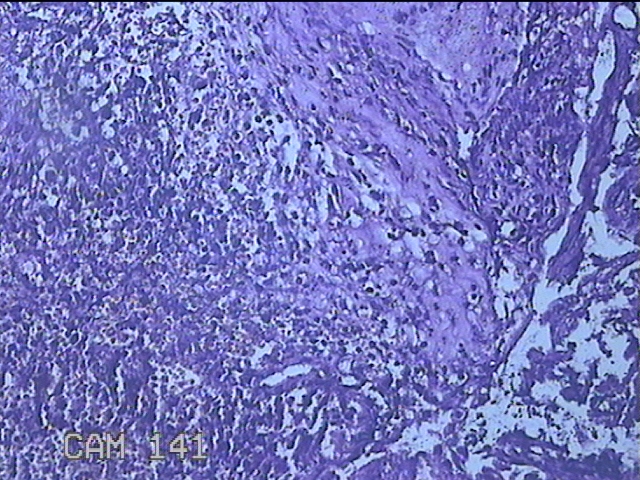

性别

女

年龄

35岁

临床诊断

根尖囊肿

一般病史

上颌包块不适2月。

标本名称

上颌包块

大体所见

灰白暗红色囊性包块1.8x0.8x0.3cm四个,表面光滑,部分已切开,囊内容物已流失,囊壁厚0.1cm。